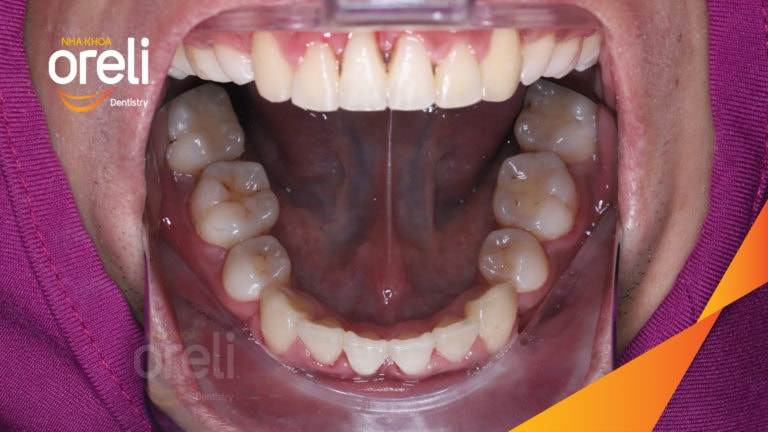

Ca niềng chỉnh cắn sâu không nhổ răng kết quả cười đẹp sau hơn hai năm tại Oreli Niềng răngCắn sâu Xem thêm